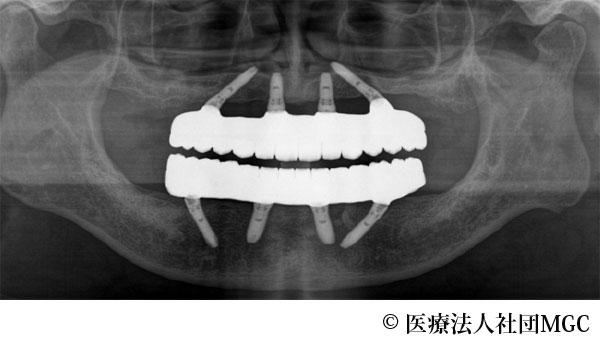

【症例5】上下All-on-4(オールオンフォー)

- 治療前

- 治療後

- 治療名

- 上下All-on-4(オールオンフォー)

- 費用

- 7,208,300円(税込)

- 期間

- 6ヵ月

歯を全体的にきれいに治してほしいとご来院されました。

ご相談の結果、患者様の生活の質(QOL)を向上させ、しっかり噛め、審美的にも重視した、上下All-on-4(オールオンフォー)を行いました。

機能性、審美性ともに改善し、満足していただけました。